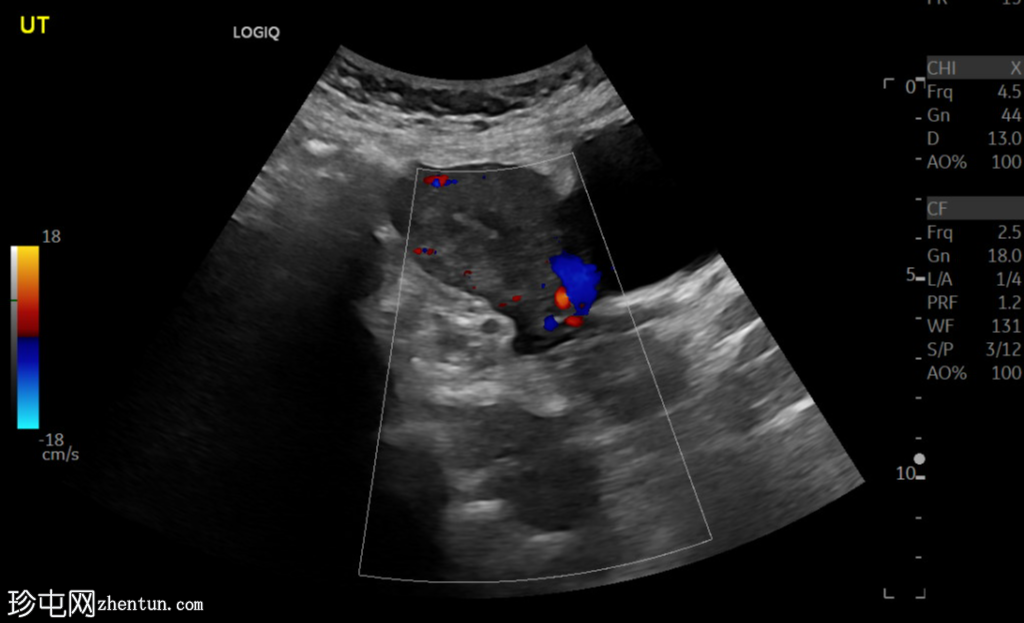

超声检查

横切面

左侧卵巢明显增大,可见一囊肿,大小约3.2 x 2.3 cm,呈火环征,可能为黄体囊肿。左侧卵巢与子宫之间可见一管状结构,直径约1.3 cm,内含浑浊液体,未见血管,最可能为输卵管积血。以上特征提示可能为左侧异位妊娠。

未见宫内妊娠囊。